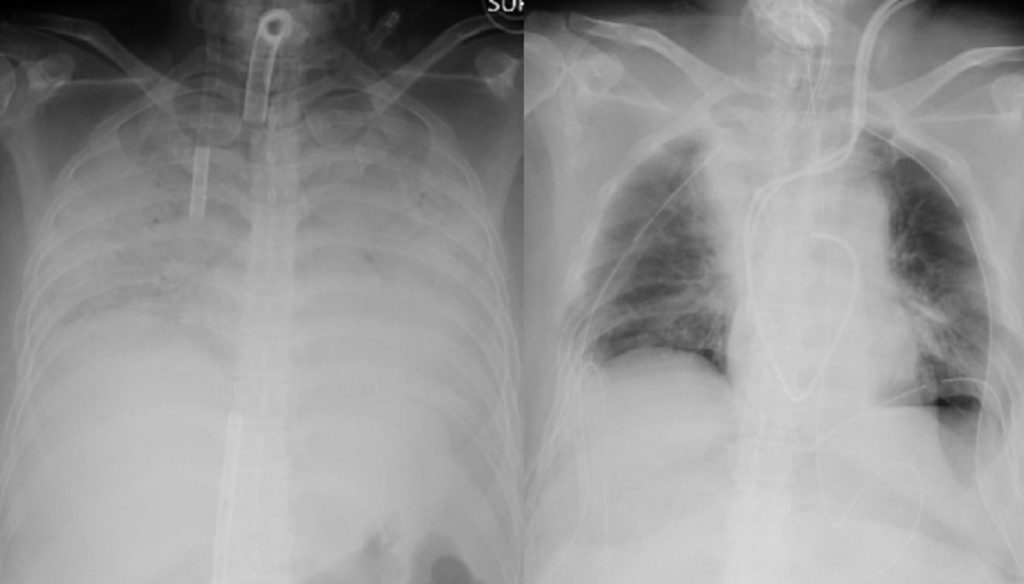

সিএনএন জানিয়েছে, করোনাভাইরাসে ফুসফুস ক্ষতিগ্রস্ত হওয়া এক নারীর শরীরে তার স্বামী এবং সন্তানের ফুসফুস প্রতিস্থাপন করা হয়েছে। চিকিৎসা বিজ্ঞানে ফুসফুস প্রতিস্থাপনের ঘটনা এর আগেও ঘটেছে। তবে ব্যতিক্রম হচ্ছে জাপানের এ ঘটনায় জীবন্ত ব্যক্তির ফুসফুস করোনা আক্রান্ত রোগীর দেহে প্রতিস্থাপন করা হয়েছে।

জাপানের কোয়োটা ইউনিভার্সিটি হাসপাতাল কর্তৃপক্ষ জানায়, সম্প্রতি ওই নারীর শরীরে করোনা সংক্রমণের ফলে তার ফুসফুস দুটি মারাত্মকভাবে ক্ষতিগ্রস্ত হয়। এতে তার বেঁচে থাকার সম্ভাবনা ক্ষীণ হয়ে পড়ে। পরে এই হাসপাতালের চিকিৎসকরা সিদ্ধান্ত নিয়ে ওই নারীর স্বামী ও ছেলের সুস্থ ফুসফুস তার দেহে প্রতিস্থাপন করতে সফল হন। ৩০ জন বিশেষজ্ঞ চিকিৎসকের জটিল এই অস্ত্রোপচার করতে সময় লেগেছে প্রায় ১১ ঘণ্টা।

হাসপাতাল কর্তৃপক্ষ জানিয়েছে, ডোনার জীবিত অবস্থায় সফল ফুসফুস প্রতিস্থাপনের ঘটনা বিশ্বের ইতিহাসে এটাই প্রথম। ফুসফুস প্রতিস্থাপনের এই পুরো অপারেশন যার নেতৃত্বে হয়েছে তার নাম ড. হিরোশি ডেট।

করোনার ফলে ওই নারীর নিউমোনিয়া হয়ে গিয়েছিল। তবে সফল অপারেশনের পর ড. হিরোশি এখন আশা করছেন দ্রুত সুস্থ হয়ে উঠবেন ওই নারী।